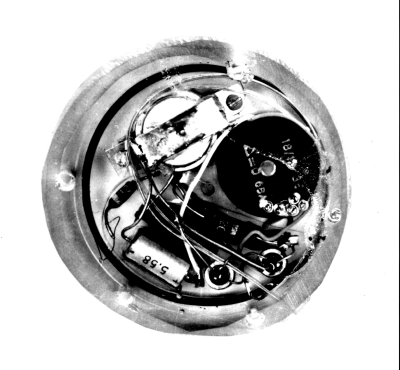

• El Marcapasos

El Marcapasos

En Suecia el Dr. Ake Senning consiguió un éxito al implantar un pequeño estimulador eléctrico bajo la piel del paciente, el aparato fue diseñado por el Dr. Rune Elmquist. Esto constituyó un enorme paso adelante, a pesar de que la batería tenía que cargarse desde el exterior una vez por semana.